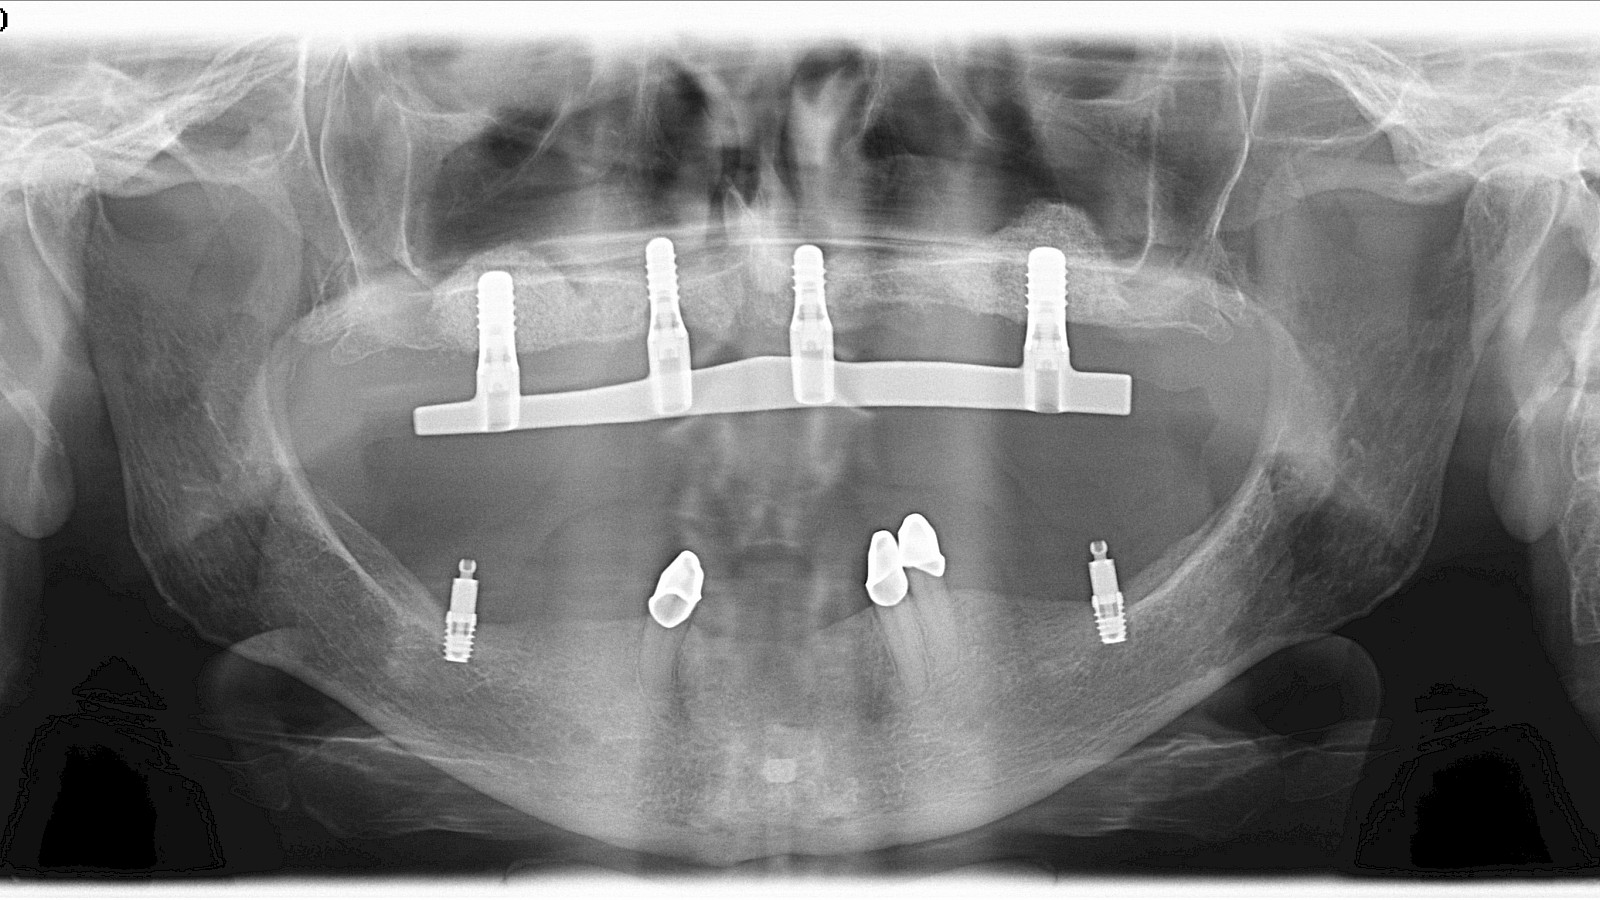

• Hands-on training for intraoral scanning, AI-based provisionals printing, model-based training implant placement and use of the Locator Fixed® system

• Two Live surgeries of complex cases with interactive discussion

4. Overdentures versus full-arch prostheses

7. The Bernese Concept for overdentures

The curriculum features live surgeries, interactive lectures, and extensive hands-on training, including implant placement on models, impression-taking, and digital design exercises.